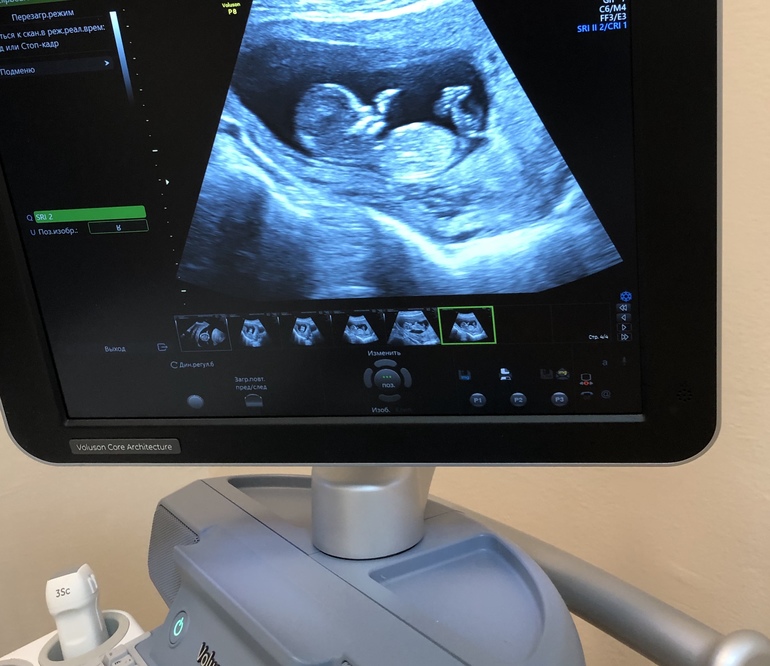

Девочки здравствуйте , сходила сегодня на первый скрининг ттт все хорошо по узи ))) но даже предположительно пол не сказали , знаю тут есть спецы которые разбираются))если не затруднит по смотрите может увидите кто )))

Тут не видно половой бугорок, увы... и мне в 14 недель сказали пол, все зависит от оборудования и специалиста, я правда верить не хотела, надеялась на ошибку))

Ой на таком сроке это как пальцем в небо. Тем более, что там ножками все закрыто

Покажет уже скорее всего ) вообще мне на 1 скрининге не ошиблись, врач очень хороший, потом сестра к ней же пошла и ей тоже пол сказали правильно, многое зависит от врача ) а так визуально там маленький отросточек который либо смотрит вверх либо параллельно телу вниз, соответственно в 1 случае мальчик во 2 девочка

Я что-то полового бугорка не вижу, ножкой что-ли закрывает..